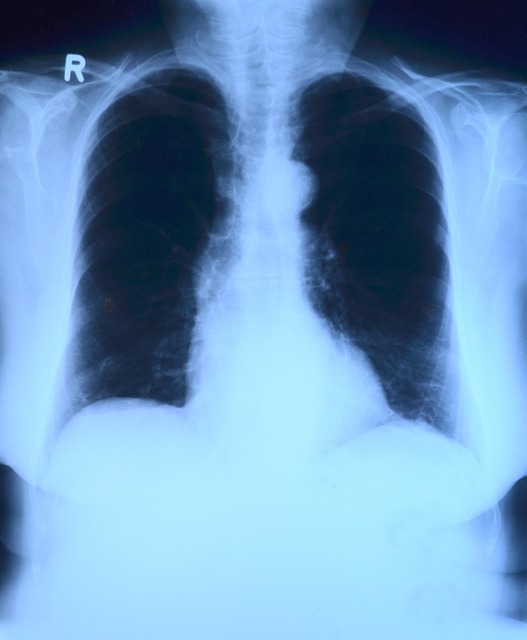

폐암은 암 중에서 치사율이 가장 높으며 수술이 가능할 때 발견하기 어렵습니다. 수술 시기를 놓쳤거나 수술 후에도 림프샘 전이의 위험이 있는 환자는 방사선치료가 필수적입니다. 수술할 수 없는 환자의 경우나 말기 환자도 호흡곤란, 환자의 통증 등을 완화하고, 종양 부위의 국소 치료로 생명을 연장함으로써 환자에게 도움을 줄 수 있습니다.

대부분 폐암의 방사선치료에 있어서는 원발 병소뿐만 아니라 mediastinum과 폐문림프샘을 포함해서 치료합니다. 다행히 종양이 폐의 상엽에 있을 경우, 적절한 크기의 조사 면으로 종양과 림프샘을 포함하여 방사선치료를 할 수 있습니다.

반면 하엽에 존재할 경우, 심장과 정상 폐 조직의 선량을 고려하며, mediastinum과 림프샘을 포함해야 하므로 조사 면이 커지고 차폐물이 복잡해지는 등의 문제가 있습니다.

종양 선량을 크게 하고 정상 폐 조직이나 척수(spinal cord), 심장에는 선량을 최소화해야 합니다. 등 뒤에서 척수를 차폐하는 방법은 mediastinum에 있는 종양을 차폐할 우려가 있기에 적정한 종양 선량을 위하여 사조사(oblique)나 측면(lateral) 조사 면과 전후(AP/PA) 조사 면으로 치료하고 있습니다.